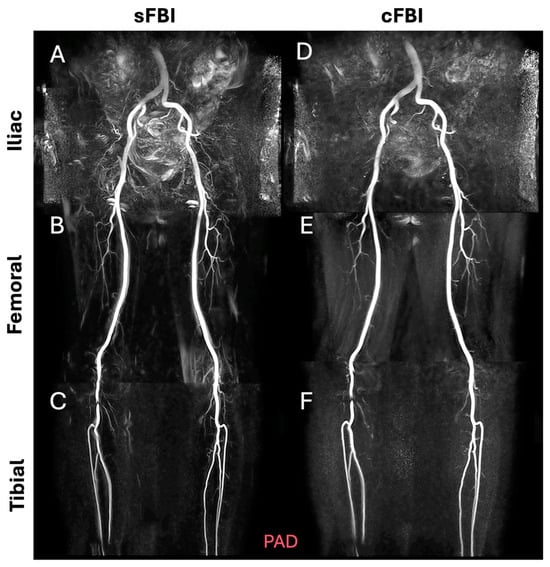

Three-Station Non-Contrast MR Angiography of the Lower Extremities Using Standard and Centric Fresh Blood Imaging

3. Results